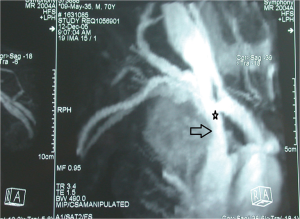

In the preoperative management of NSCLC involving SVC extension of the infiltration can be studied with cavography with simultaneous injection of contrast agent from both upper limbs, even if this technique might be heavily biased by the presence of overlaying structures which might results in inconclusive images (33,34). Recently, CT angiography (CTA) and magnetic resonance angiography (MRA) has been proposed to assess vessel involvement (Figure 1). Both CTA and MRA showed a higher sensibility compared to cavography in discriminating different anatomical structures and eventually extent of vascular invasion (33); interestingly, some authors reported a similar sensibility both for un-enhanced and enhanced MRA, which might further reduce invasiveness of the test (35,36). Additionally, Ohno and colleagues (37) report a better quality of radiological images with the use of electrocardiographically (ECG)-triggered MRA. Lastly, a echocardiography is mandatory to exclude the presence of thrombus in the right atrium (34).